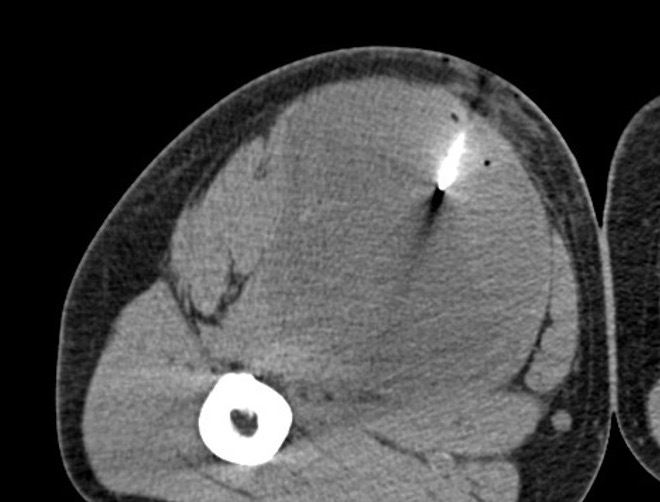

Biopsy critical

- core needle biopsy under image guidance in tract of future surgical resection

CXR, CT chest / abdomen

+/- bone scan, PET scan